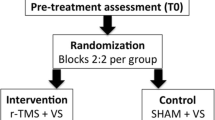

Stimulation points and mapping procedure

Our mapping template contained 52 cortical spots per hemisphere, distributed to brain areas by use of the cortical parcellation system (CPS; Fig. 2, Table 1) (Corina et al. 2005). As reported recently, some brain regions could not be stimulated because stimulation is known to trigger unacceptable pain, i.e., the orbital part of the inferior frontal gyrus (orIFG), polar and anterior frontal regions (polFG, aSFG, aMFG), the polar temporal gyri (polTG) and the anterior middle temporal gyrus (aMTG). The inferior temporal gyrus (ITG) was not stimulated because stimulation is known not to trigger comparable effects due to increased distance to the skull and decreased stimulation intensity in the brain (Hauck et al. 2015a; Krieg et al. 2013). We anatomically identified the spots within both hemispheres in each subject’s 3-D MRI reconstruction and tagged them as stimulation points prior to each volunteer’s mapping. First, the baseline session was performed as mentioned above, then the mapping session was conducted as follows: Each hemisphere was stimulated twice, taking it in turns and starting with the left hemisphere; each stimulation point was stimulated 5 times, thus 10 times in total. For a maximal field induction the stimulation coil was placed tangentially to the skull in anterior-posterior field orientation (Epstein 1996; Lioumis et al. 2012; Miranda 2013).

We determined a mean RMT of 34.9 ± 8.9 % maximal stimulator output for the left hemisphere and of 34.5 ± 8.2 % for the right hemisphere (p = 0.9274; Table 2). Due to reported pain, we reduced the stimulation intensity after RMT determination in two cases (marked with an asterisk). Yet, the electric field strength on cortical level was higher than 55 V/m at all times and we did not observe any effect on error occurrence or frequency in these subjects compared to the whole collective as observed previously (Picht et al. 2013). All subjects tolerated the mapping well; mean discomfort was comparable for both hemispheres. During baseline testing 94.3 ± 4.1 % of the pictures were answered correctly, and the individual mapping task set consisted of 68 pictures on average. The number of baseline errors did not correlate with the number of errors during mapping conditions.

Comparison of the two hemispheres

Error occurrence for the two hemispheres was comparable (p = 0.2314). Pooled across all subjects, 5122 stimulations of the left hemisphere could elicit 163 errors, equivalent to a mean total ER of 3.2 ± 1.6 %. Concerning the right hemisphere, we observed 182 errors during 5126 stimulations (ER of 3.6 ± 1.7 %). Subject rates per cortical spot ranged from 0 to 6 positive out of 10 stimulated subjects within the left hemisphere and from 0 to 5 within the right hemisphere (p = 0.6445; Tables 3 and 4).